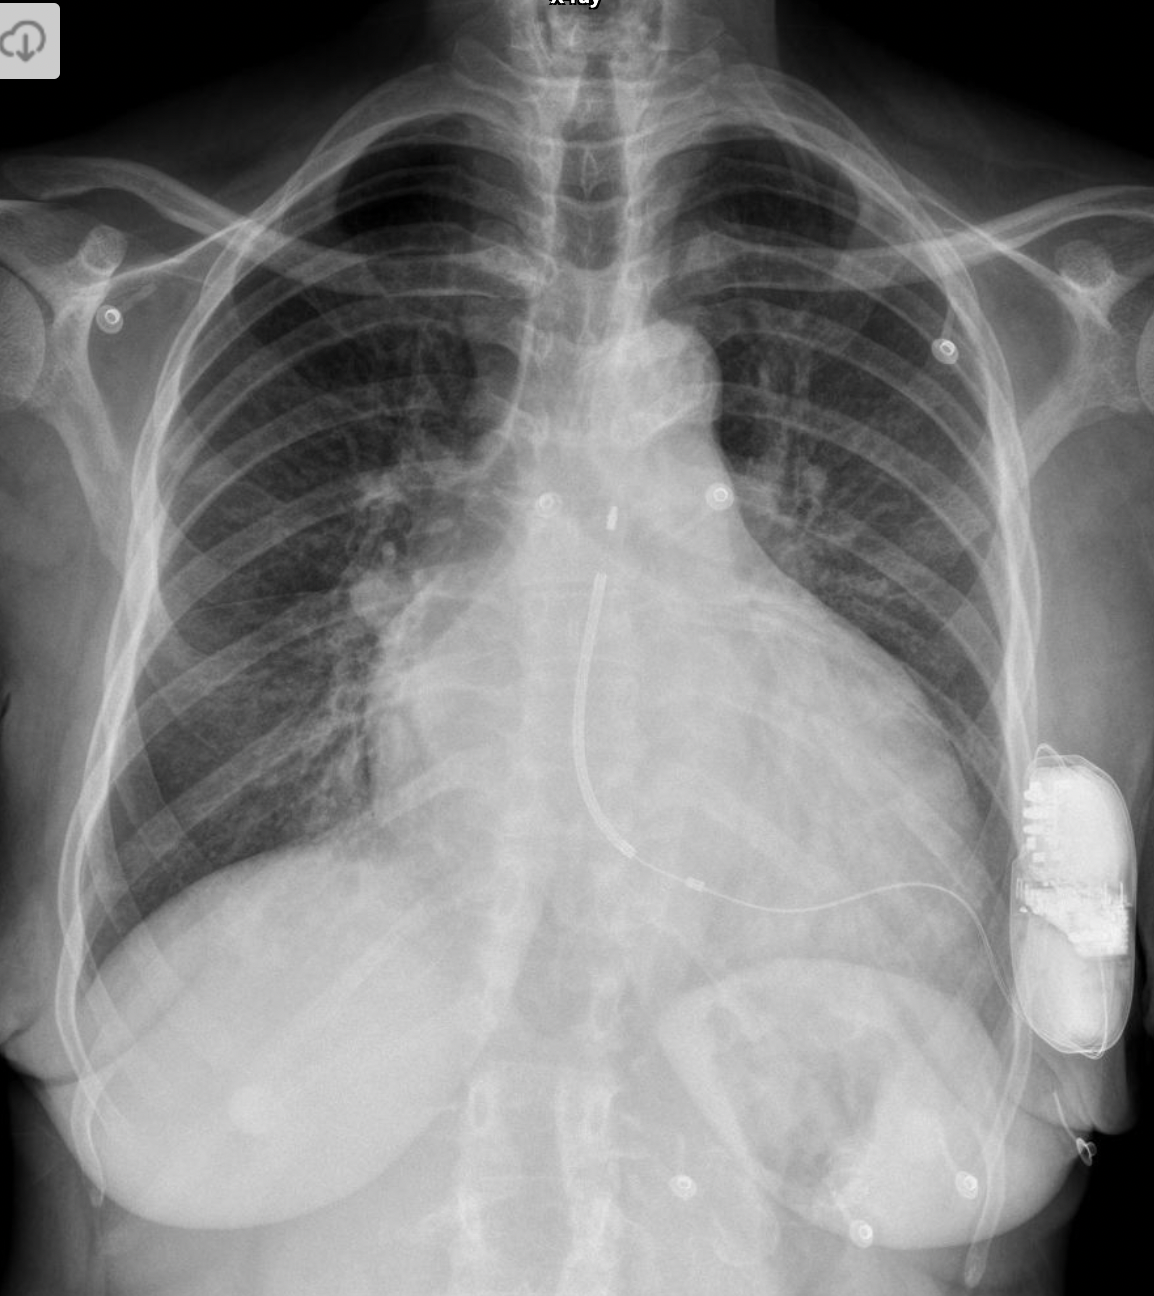

15

Q

A

-Dual chamber ICD

-LVAD implanted